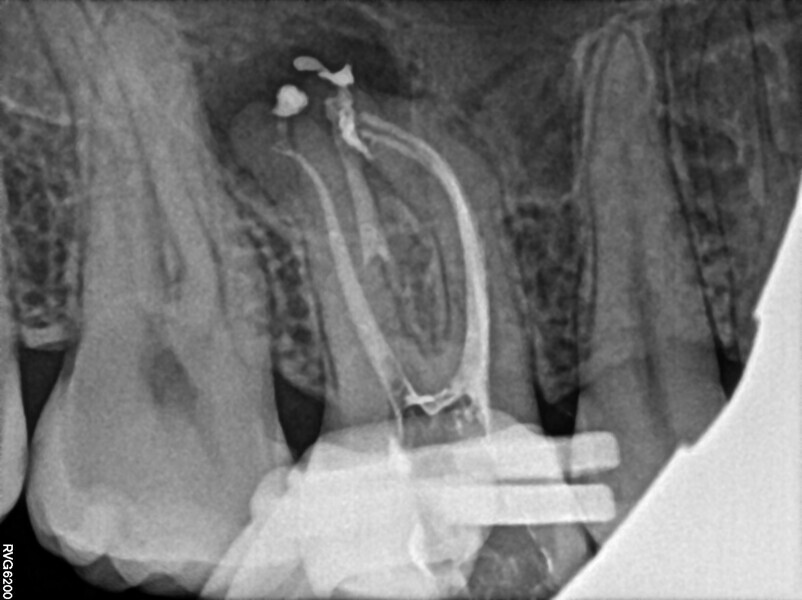

A 25-year-old female patient presented to the office owing to constant pain related to the mandibular left first molar. Pulp necrosis was diagnosed. After the emergency appointment, the patient was referred for complete treatment. The tooth was treated in the same manner as described in the previous paragraphs. After creation of the access cavity, the orifices were located. In the root chamber, the orifices of the MB, mesiolingual, DB, distomesial and distolingual canals were present. After pre-flaring and preparation of the middle third, the LPE enhanced irrigation protocol with the SkyPulse laser was performed. After the irrigation protocol in the mesial root, the irrigants started to flow between lingual and buccal canals. Such an observation suggested to the operator that some space in the isthmus had been created. It is worth mentioning that at this stage apical enlargement was not performed. Final preparation of all five canals was performed with the reciprocating file, and the final irrigation protocol was performed as in the previous case. The radiograph clearly revealed that the isthmus space was filled with the sealer. The radiograph and CBCT image revealed that there were four portals of exit in the mesial root.